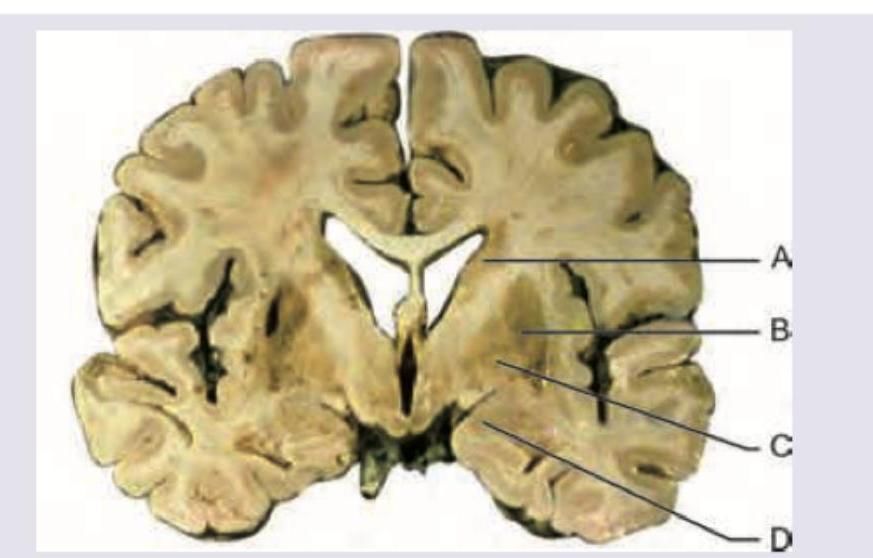

Which of the following sites in the most common site of intraparenchymal bleeding?

Explanation: ***B*** - Label B points to the **lenticulostriate arteries** territory, specifically within the **basal ganglia**, including the putamen. The **putamen** is the **most common site** for spontaneous intraparenchymal hemorrhages, often due to **hypertensive vasculopathy** affecting these small penetrating arteries. - Hypertensive hemorrhages typically occur in areas supplied by small-caliber perforating arteries, which are particularly susceptible to the effects of chronic hypertension, leading to **lipohyalinosis** and microaneurysms (Charcot-Bouchard aneurysms) that rupture. *A* - Label A points to the **corona radiata** or surrounding white matter. While intraparenchymal bleeds can occur here, it is less common than in the basal ganglia. - Hemorrhages in the corona radiata would be more consistent with **lobar hemorrhages** which are often associated with **cerebral amyloid angiopathy** in older patients. *C* - Label C points towards the **thalamus**. The thalamus is one of the common sites for intraparenchymal hemorrhage, particularly due to hypertension, but it is less frequent than the putamen. - Thalamic hemorrhages often present with distinct clinical syndromes, such as **sensory deficits** and eye movement abnormalities, due to the critical structures located here. *D* - Label D points to the **temporal lobe cortex** and subcortical white matter. Lobar hemorrhages can occur in the temporal lobe, but they are not the most common site overall for intraparenchymal bleeding from all causes. - Temporal lobe hemorrhages can be caused by various factors, including **cerebral amyloid angiopathy**, vascular malformations, or trauma, but hypertensive bleeds rarely occur in the cortex.